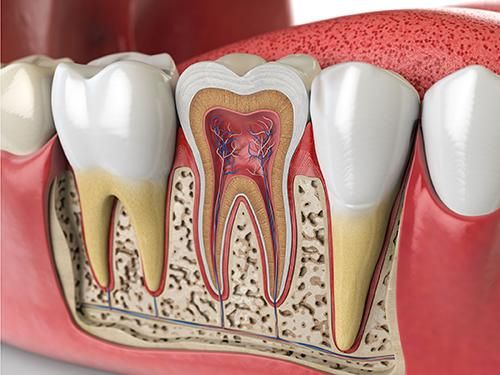

치아가 시린이유 - 마모증

안녕하세요 목동안치과의 안상우 원장입니다.여러분은 어느날 이유가 없이 치아가 시린적이 있으셨나요?치아에 이상이 없음에도 불구하고 시린증상이 있다면 마모증이 있을수 있습니다.치아의 시린증상이 생기는 현상에 대해서 알기 위해서는 치아의 구조에 대해서 알아볼 필요가 있습니다.치아는 보시는것과 같이 머리와 뿌리가 있구요.치아의 뿌리를 잇몸 안에 들어가 있습니다.치아 표면에는 법랑질이라는 단단한 조직이 있고 안쪽에는 상아질이라고 하는 상대적으로 연한 치아 조직이 있어요.이 상아질은 모세관현상에 의해서 신경에 자극을 가할수 있는 구조로 되어 있습니다.치아 안에는 신경이 들어가 있지요.결과적으로 시리다는것은 이 신경이 외부 온도변화에 의해서 자극이 되고 있다는 것입니다.치아의 옆부위가 깎이거나 쓸리는 작용에 의해서 표면이 깎여 나가게 되고 상아질이 외부로 노출이 된다면 치아 안의 신경이 외부에 가까워지면서 온도변화에 민감하게 되는것이지요.이런 증상을 마모증이라고 합니다.마모증은 우리가 직접확인을 할수도 있습니다 손톱으로 치아 옆부위를 긁어 보셔서 뭔가 걸리는것이 있다면 마모증이 있는것일 가능성이 높아요.마모증은 우선적으로 칫솔질을 잘못된 방향으로 할때 생기게 됩니다.우리가 칫솔질을 할때 보통 좌우로 하는경우가 많아요. 치약은 부드러워 보이지만 안에는 치아 표면의 이물질을 제거하기 위해서 까글까끌한 연마제가 들어 있습니다.이 마모제가 들어간 치약을 치아의 옆면을 자극하게 되면 표면이 깎여 나가면서 마모증이 생길수 있어요.이렇게 생긴 마모증은 보통 옆면이 U자형태로 나게 됩니다.또다른 원인으로는 치아에 과도한 힘이 가해지는 경우에 마모증이 생길수 있어요.우리의 치아는 매우 단단하지만 힘이 가해지게 되면 눈에 보이지 않을 정도로 매우 미세하고 휘고 있습니다.너무 강한 힘에 의해서 치아가 과도하게 휘게 되면 치아의 옆부위가 깎이면서 마모증이 발생하게 되요.이런 과도한 교합력에 의해서 생기는 마모증은 보통 도끼로 찍은 이런형태로 생기게 됩니다.또다른 원인으로는 잇몸이 내려갔을 경우에도 시린증상이 생길수 있습니다.아까 모세관 현상을 일을킬수 있는 상아질이라는 조직이 있다고 말씀드렸잖아요?치주병에 의해서 잇몸이 내려가게 되면 이 상아질의 노출범위가 넓어지게 되어 시린증상이 나타날수 있어요.시린증상을 줄이기 위해서는 이런 원인들을 제거해 줘야 합니다.우선 칫솔질로 생기는 마모증은 칫솔질을 할때 치아에 너무 강한힘을 주지 마시고 치아가 난 방향으로 약한힘으로 칫솔질을 해야 합니다. 일단 마모증이 생기게 되면 해당부위가 재생되거나 하지 않기 때문에 시린증상으로 인해서 불편감이 있다면 치과재료로 충전을 해줄수 있어요또한 힘에 의해서 생기는 도끼 형태의 마모증은 치아에 가해지는 힘을 줄여야 합니다.지속적으로 치아에 과도한 힘이 가해지다보면 이런마모증이 심해지다가 결과적으로 치아가 부러지는 현상이 발생할수 있어요.마지막으로 잇몸이 내려가서 생기는 시린증상입니다.치아를 둘러쌓고 있는 잇몸이 없어지게 되어 치아 뿌리가 드러나게 되면 치아가 시릴수 있어요. 제일 좋은것은 잇몸이 내려가지 않는것이 좋지만 염증이나 그외의 원인으로 잇몸이 내려가서 시리게 되었다면 치아표면을 코팅하는 약제를 이용하여 시린증상을 완화할수 있습니다.마모로 인해서 시린치아의 치료방법은 아까 말씀드린것처럼 마모가 된 부위를 충전해 주는것입니다.치아를 충전하는 재료에는 레진이라는 재료와 GI라고 하는 재료가 있어요.레진이라는 재료는 보험적용이 되지 않아서 충전시에 비용이 조금비쌉니다. 하지만 색상이 치아와 거의비슷하고 강도가 좋아요. 레진은 비보험 진료기 때문에 병원마다 비용에 차이가 있을수 있는데 치아 하나를 치료하는데 보통 8~12만원정도 합니다.GI라고 하는 글래스아이오노머라고 하는 보험이 적옹되는 재료도 있는데요이재료는 레진보다 색상이 조금 밝고 강도가 약하긴 하지만 보험적용이 되기 때문에 약 8천원정도의 비용으로 치료를 할수 있습니다.잇몸이 내려가서 시린 치아는 잇몸의 염증을 줄이도록 해야 하고 뿌리가 드러난 부분은 치과용 약제를 도포해서 시린증상을 줄일수 있습니다치아가 시리다면 시린원인을 제거해 줘야 합니다.칫솔질이나 과도한 힘같은것 말이죠.또한 잇몸이 내려가는것을 방지해서 치아의 뿌리가 노출되지 않도록 하는것이 좋습니다.또한 마모된부위는 치과용재료로 충전을 해서 시린증상을 줄이는방법도 있어요.올바른 칫솔질과 관리로 마모증이 생기지 않도록 해준다면 치아가 시린증상을 예방할수 있습니다.치아관리 잘 하셔서 꼭 마모증이 생기지 않도록 해주세요.